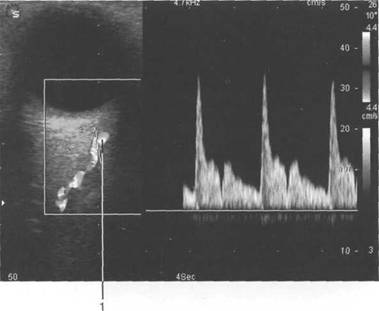

(a. ophtalmica).

(v. ophtalmica).

arteria ophtalmica;

При сонографии отчетлив 121h711b о выявляется чивается хрусталиком, а сбоку - ресничным

четлив 121h711b о дифференцировать зрительный нерв и глазодвигательные мышцы (рис. 2.16, 2.17).